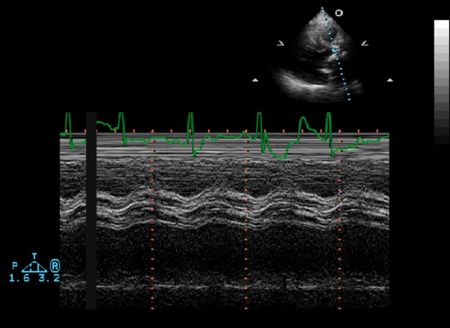

Ventricular M-mode

- Ventricular Wall Thickness

- Ventricular Chamber Size

- Intraventricular Masses